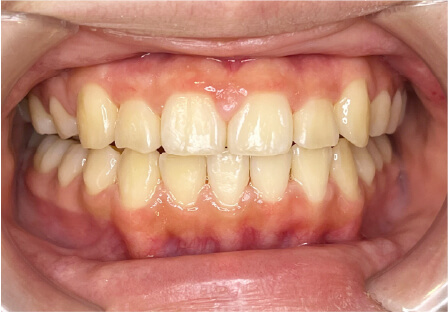

叢生の症例

28歳

女性

相談内容

カウンセリング・診断結果

IPR承諾、アレルギー無

治療内容・方法

全顎アライナー矯正

術後の経過・現在の様子

クリアライナー使用

治療のリスク

痛み・歯根吸収・歯肉退縮・虫歯・後戻り

費用・治療期間

990,000円、3年